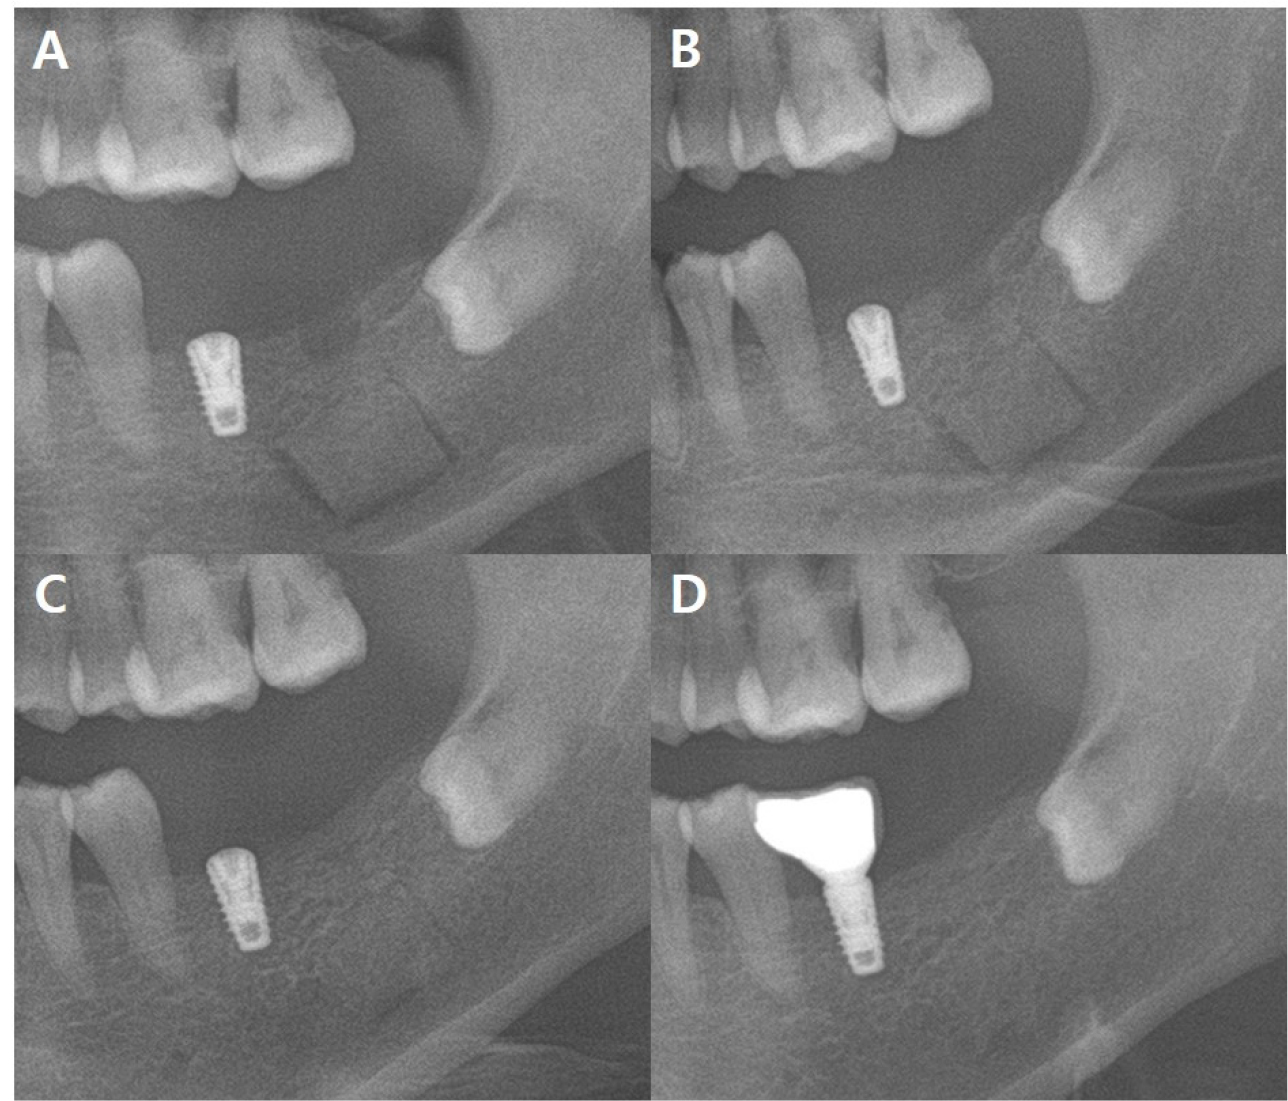

Approximately one month after the event, sensation on the right side of the lip and chin was 20–30% lower than that on the left, and the patient complained of a burning or dull feeling. The implant fixture was removed under intravenous sedation using a full-thickness mucoperiosteal incision in the buccal and posterior mucosa in the #45–47 region. Lateral subperiosteal dissection was performed to expose the right mandibular body. A bony window was created using Piezosurgery® (Mectron, Carasco, Italy) to minimize the bony gap. In addition, the inner aspect of the bony window was narrowed as much as possible to obtain sufficient stability without additional plate fixation; therefore, no additional surgery was required (Figs. 1B and 3). The implant was attached to the IAN, and dissection between the nerve and implant was performed prior to extracting it from the bone marrow. A fibrin sealant was used to cover the implant removal site and secure the bony window in its original position (Fig. 4).

Prednisolone 10 mg four times a day for seven days and mecobalamin twice daily for seven days were prescribed two days after the event. The implant in the #37 region was surgically removed under general anesthesia 10 days after the event. The surgical technique was similar to that in Case 1. To minimize nerve damage, implant removal was performed by creating a bony window in the left buccal bone (Fig. 6) using Piezosurgery® (Mectron, Carasco, Italy). After implant removal, the bone was fixed without a plate. Although the patient could not directly express discomfort due to intellectual disability, sensory differences could be confirmed through reactions such as continuous contact with the lip. Because she had an intellectual disability, it was not possible to observe minute sensory changes through nerve mapping, as in Case 1. Postoperatively, prednisolone (5 mg four times a day ) was prescribed for 5 days. At the 2-month follow-up, mecobalamin (500 µg twice a day) was prescribed for 90 days. The 10-month follow-up image revealed adequate bone healing (Fig. 7). The patient did not show any abnormal behavior such as touching the lips, which could suggest paresthesia.

Piezosurgery minimizes soft tissue damage in oral surgery16 and enables precise bone removal by oscillating with an ultrasonic frequency17. In addition, unlike existing bone-reduction devices such as high- and low-speed turbines, there is no thermal damage. 18 In both our cases, a piezosurgical device was used for bone removal. The position of the sunken implant fixture was accurately determined using CT, a bony window as small as possible was created, and sufficient fixation without plate fixation was achieved by performing an inclined osteotomy. Bone healing was confirmed after 10 months.